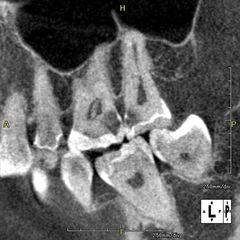

2018/10/27

セラミック治療

大臼歯の隣接面(接する部分)からの虫歯になっていました。2018.10.27

詳細はこちら

口腔外科処置

右上の親知らずの抜歯から1ヶ月経過しました。2018.10.27